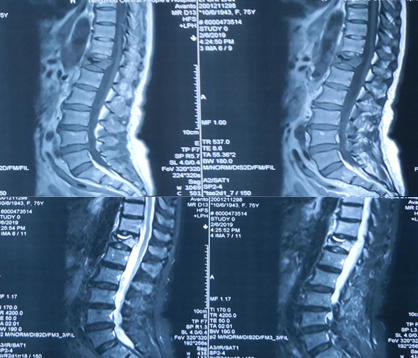

术前CT

术前MRI

术前诊断:1.胸腰椎后凸畸形,2.重度骨质疏松症,3.Kummell病II期,4.胸椎椎管狭窄,5.黄韧带骨化症,6.高血压病。

术后CT

•      术后3月CT